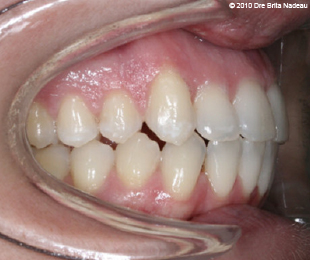

Marie-Hélène Cyr - Left lateral intraoral view - After orthodontic treatments and orthognathic surgeries (January 29, 2010)

January 29, 2010 - My final class I occlusion contrasts with the 2005 left lateral view.